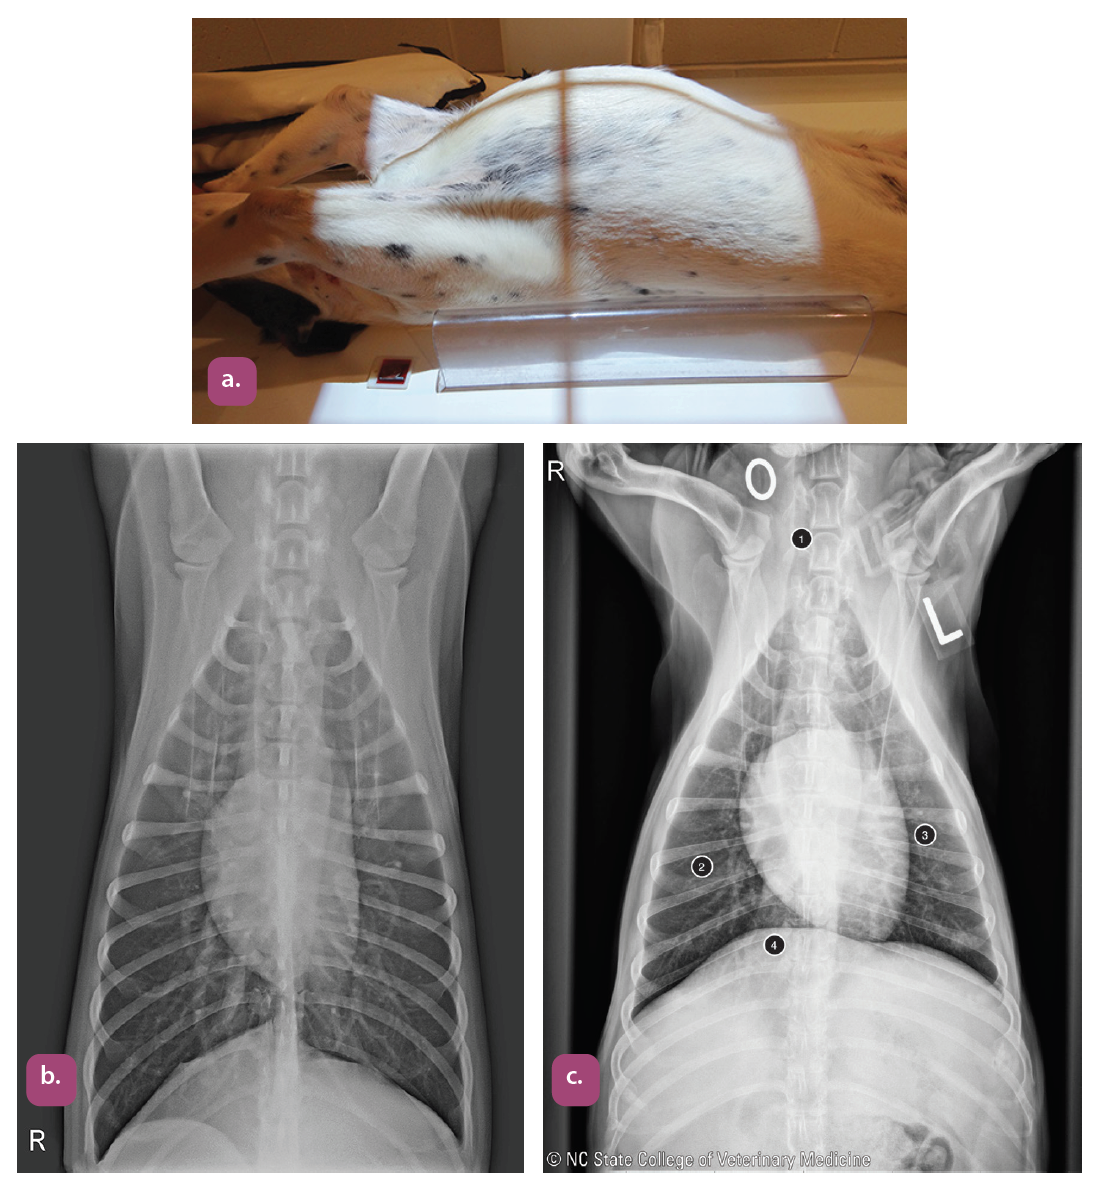

ventrodorsal projection of the thorax